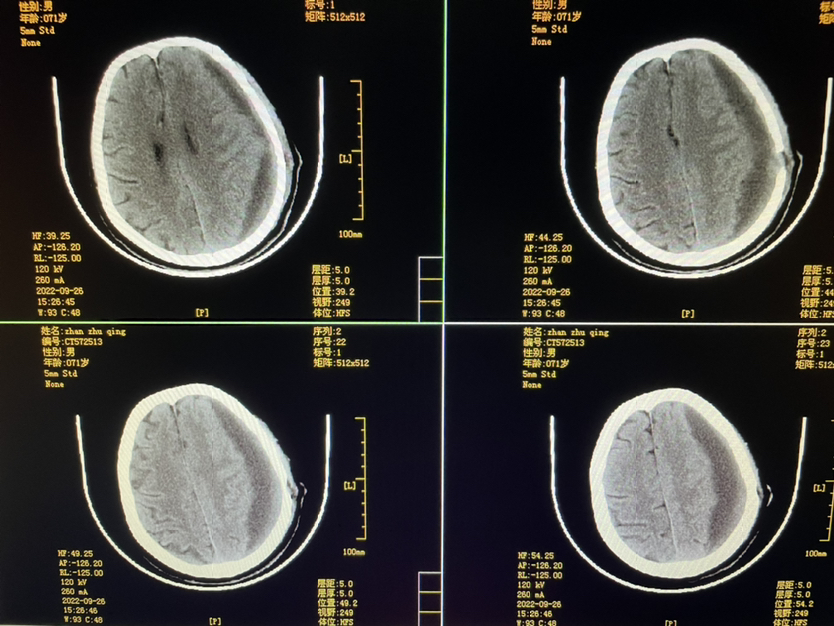

448859,头疼四肢乏力4天,71y